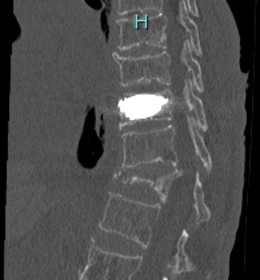

第11胸椎椎体骨折を認めます。骨折部には黒いギャップが存在し、偽関節を呈しています。軽微な後壁損傷も認めます。第1腰椎は椎体骨折後の楔状化変形を認めますが、癒合しています。

骨折部にステントの殻を挿入し、ステント内に骨セメントを充填して治療しました。背中に5mm程度の切開を2か所おいて施します。ステントにより再圧潰が防がれ、また隣接椎体に対する負担も軽減されることが報告されています。